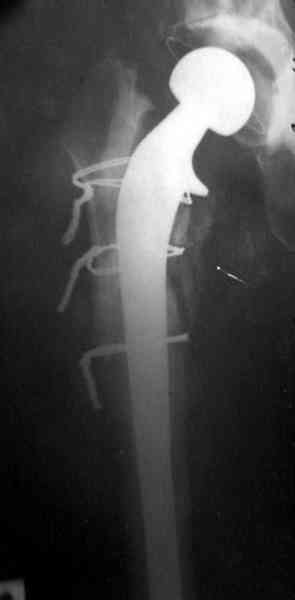

Как-то показывал случай после осложненного тотального эндопротеза,

сперва из-за отсутствия экономических возможности, а затем привыкшая

к своей участи вот уже более 8 лет ходит на временном

"протезе-спейсере".

Полость вертлужной впадины и проксимальное бедро были заполнены

custom made временным протезом из цемента.

Для бедренного компонента можно применить старую длинную ножку

протеза и желательно малого диаметра.

Цементная смесь наносится вручную на металл и затем доводится до

ровного диаметра поверхности снятием лишнего цемента шаблоном. Такие

шаблоны были в старом интрамедуллярном наборе, различные по диаметру

отверстия на металлической пластине. Протез с цементом проводится

через отверстие в шаблоне для точного совпадения с размером

проксимального римера. Таким образом приготовленный феморальный

компонент будет держаться в бедренной кости плотно.